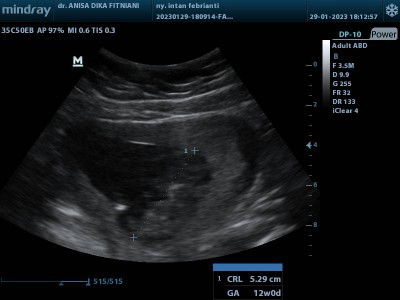

USG usia 13 week

Pagi bunda² di sini saya mau tanya bun ini hasil USG di usia 13 week nah kira² bunda ada yg pengalaman tidak tentang kelainan tentang janin bun di sini waktu blom hamil keputihan abnormal bun saya takut kehamilan saya ini ada kelainan klw dr / bidan sempat bilang klw semua sehat² bun,, tapi selama hamil sampai usia 16 week masih keputihannya bun, mau ke dr spesialis blom smpt bun ? Tolong bunda² yg ber pengalaman boleh sharing ke saya atau sarannya bun🙏